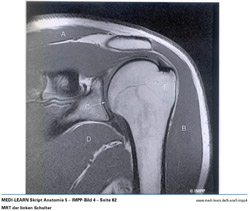

• MRT der linken Schulter